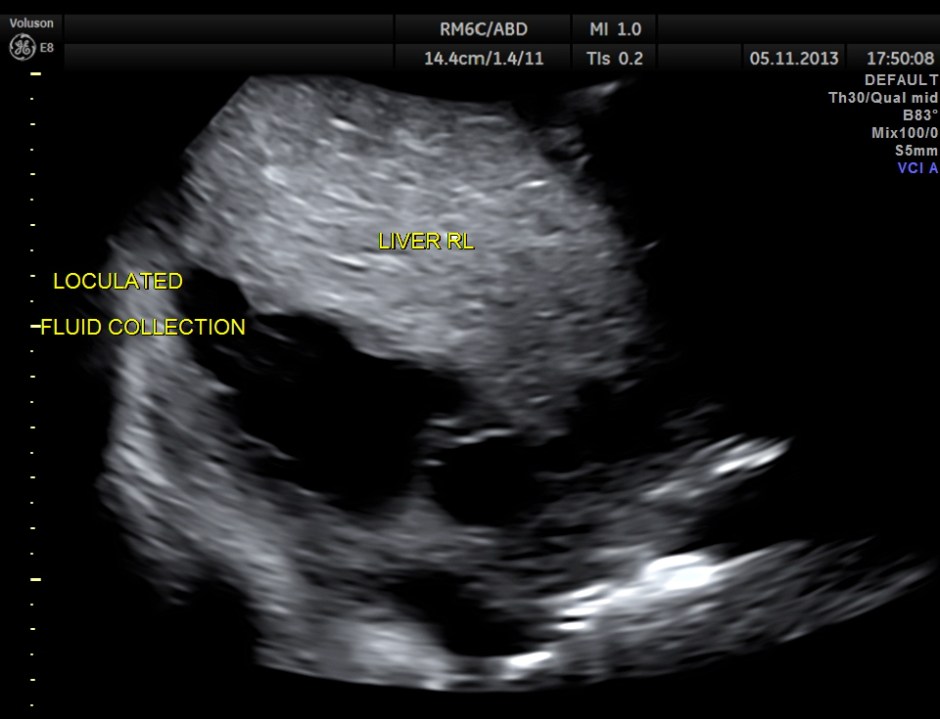

Loculated sub diaphragmatic fluid collection.

Septated cystic mass seen in the free surface of the right lobe of the liver.

This patient had a painful metastatic nodule in the right lobe of the liver. He also had loculated sub diaphragmatic collection and a septated cystic mass in the free surface of the liver.